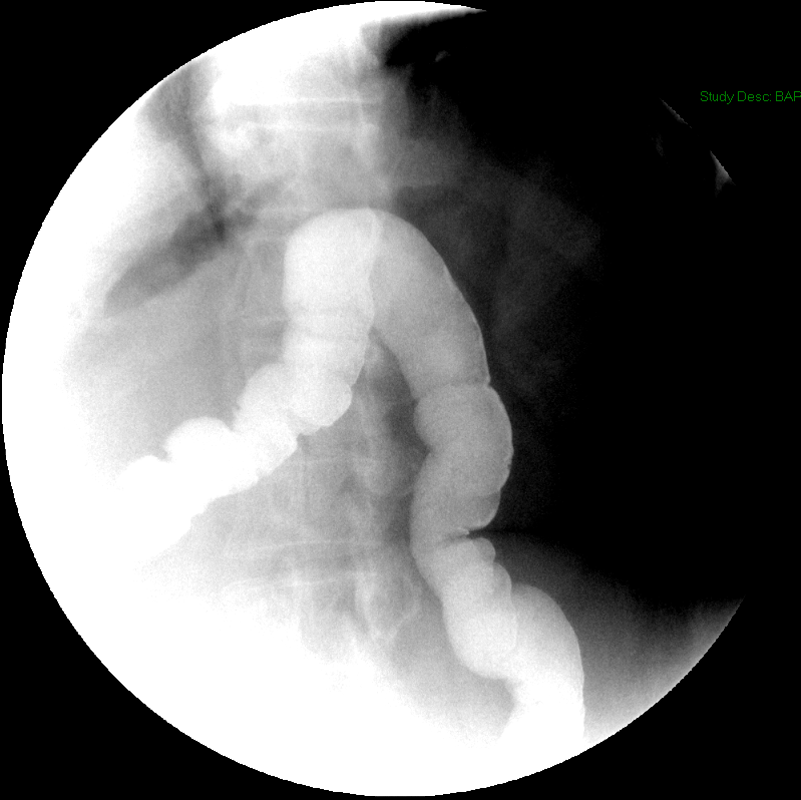

- Method:

- Place the patient in an upright LPO under the fluoroscope.

- Have the patient swallow the barium a period of 15 - 20 seconds.

- Obtain spot radiographs of the distal esophagus at 1, 2, and 5 minutes after ingestion of the barium

(key image 1)

(key image 2)

(key image 3).

- Ensure the distance between the patient and the fluoroscope is kept constant between all 3 radiographs.

- If the barium contrast material completely clears the esophagus at 1 or 2 minutes, do not take the subsequent spot images.

- If all contrast material has emptied from the thoracic esophagus the study is negative, proceed with a regular thoracic barium swallow.

- If contrast material remains in the thoracic esophagus, have the patient take some additional sips of thin barium obtaining images of the gastroesophageal junction as contrast material passes through it.

- Images are obtained in the upright LPO projection.

- Films are obtained 1 minute, 2 minutes, and 5 minutes after contrast material administration.

- If contrast has emptied from the thoracic esophagus on the one minute image, the 2 minute and 5 minute images are not needed.